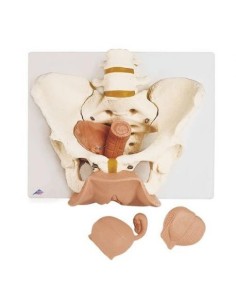

Dal cranio in 22 parti con incastri magnetici ai modelli di colonna vertebrale, da quelli di articolazioni a quelli di cuore, ogni pezzo della nostra collezione è progettato per un’immersione totale nello studio dell’anatomia umana. I nostri modelli, realizzati tramite scansioni di ossa vere, garantiscono un’esperienza tattile autentica e una fedeltà di peso quasi identica agli originali.